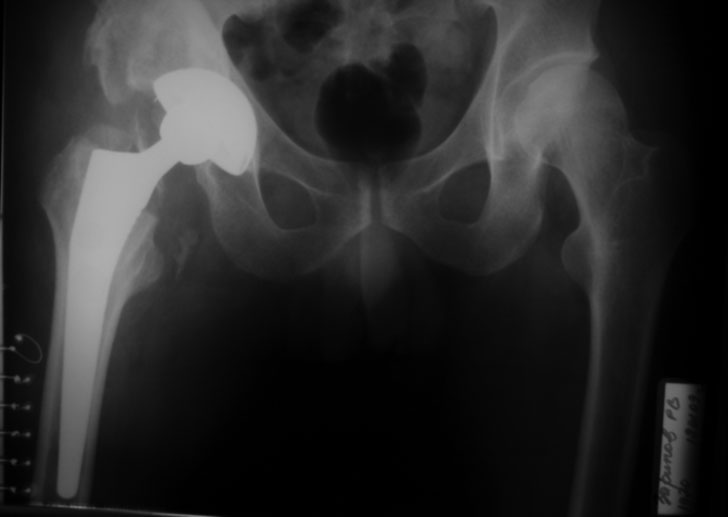

[Ortho] застарелый вывих бедра (продолжение темы http://weborto.net/forum/1226122957/index_html#1226722831)

репозиция 3 недели, артропластика Corail - Duraloc